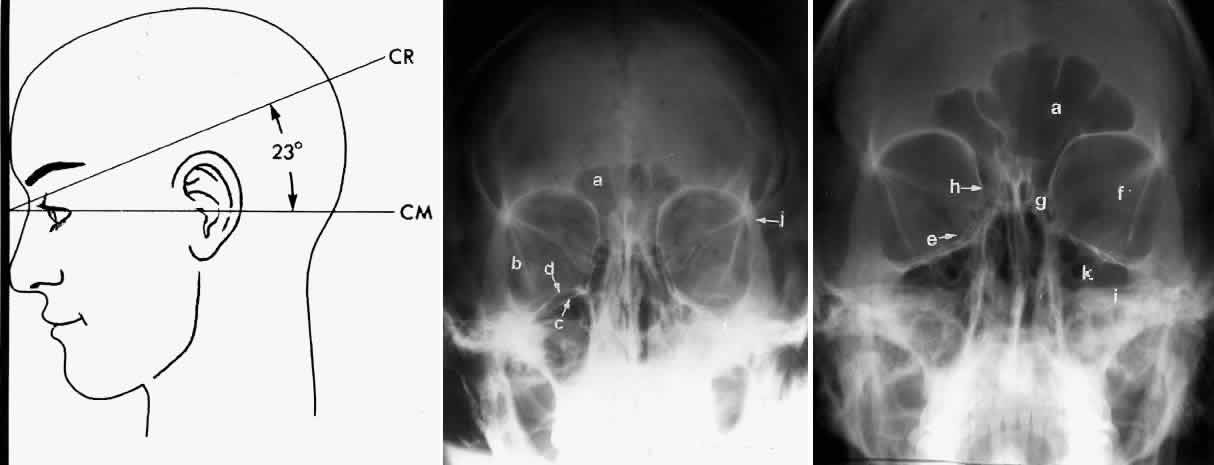

In 1918 the evaluation of the frontal and ethmoid sinuses prompted Caldwell9 to describe a projection (Fig. 3) that eliminates the superimposition of the sphenoid bone on these paranasal sinuses. The patient is positioned with both the nose and forehead against the x-ray cassette while the x-ray beam is directed downward 15 degrees to 23 degrees to the canthomeatal line.5,6,9 This orientation also projects the petrous bones inferior to the orbit, thus avoiding obscuration of the orbital structures. As in the Waters view, the Caldwell view is a posterior-anterior projection. This excellent view of the frontal and ethmoid sinuses also allows good visualization of the orbital rims, greater and lesser sphenoid wings, lacrimal gland fossa, medial orbital wall, and both the superior and inferior orbital fissures.10 The innominate line is prominent in this view and represents the depression on the temporal surface of the greater wing of the sphenoid bone where it forms the medial wall of the temporal fossa or lateral wall of the orbit. This innominate line can be straight, end with a medial right angle turn, or continue inferiorly to form the outline of the pterygoid plate.8 A lack of continuity of the innominate line suggests a fracture of the lateral orbital wall.

Fig. 3. A. Schematic showing positioning for a Caldwell projection. (CM, canthomeatal line; CR, central ray) B. Radiograph of a Caldwell projection. The petrous ridge is positioned at the orbital floor. Detail of the orbital floor and maxillary sinus is blocked. C. The radiograph is taken at a steeper angle so the petrous ridge is now positioned lower within the maxillary antrum. (a, frontal sinus; b, innominate line; c, inferior orbital rim; d, posterior orbital floor; e, superior orbital fissure; f, greater wing of sphenoid;g, ethmoid sinus; h, medial orbital wall; i, petrous ridge; j, zygomatic-frontal suture; k, foramen rotundum) (A; Rao VM, Gonzalez CF: Plain film radiography and polytomography of the orbit. In Gonzalez CF, Becker MH, Flanagan JC [eds]: Diagnostic Imaging in Ophthalmology, pp 1–7. New York, Springer Verlag, 1986)